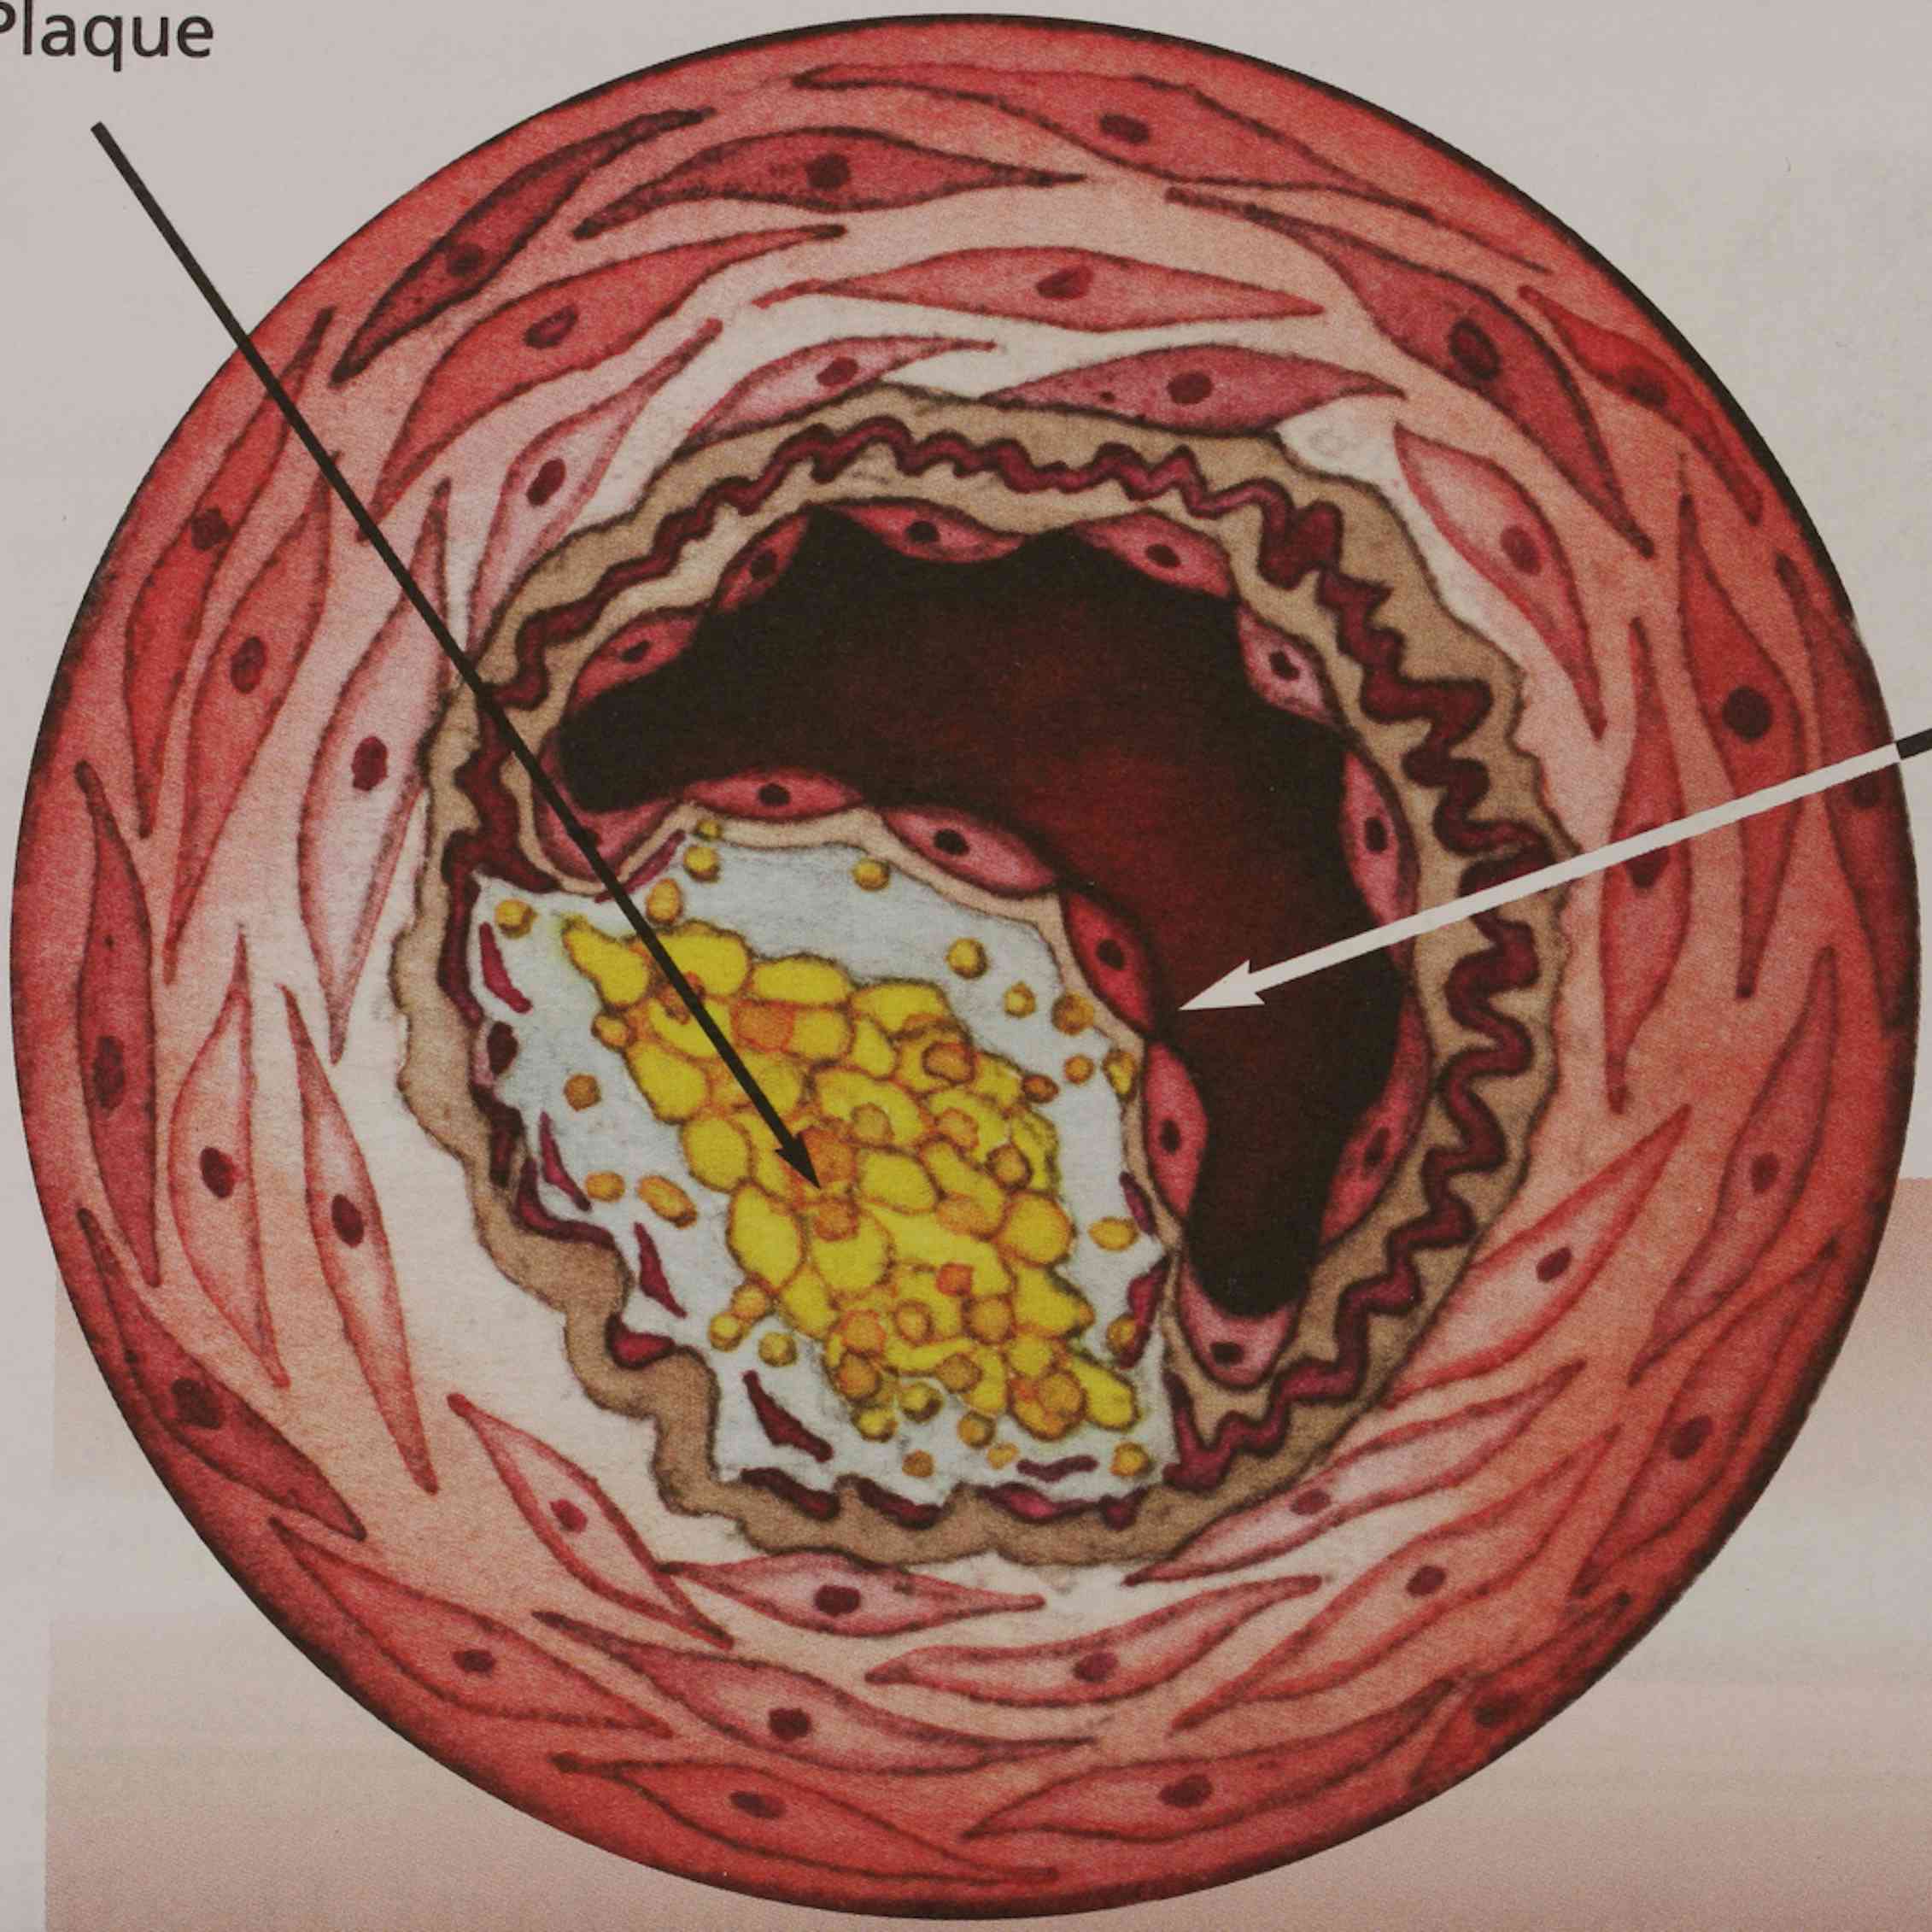

a deposit of plaque within the arterial wall

Cholesterol plaque in artery – Vida Abuelo

Artery Blockage caused by Plaque – TrialExhibits Inc.

Artery Atheroma Plaque Vector Illustration | CartoonDealer.com #20296118

Arterial plaque | Serrapeptase